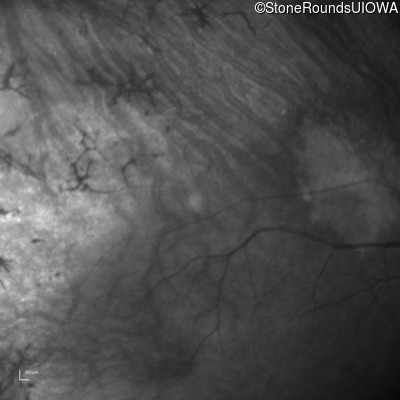

Infrared Fundus Photograph - Right - 20/32 +2 sc

Exemplar

Infrared Fundus Photograph - Left - 20/25 -1 sc